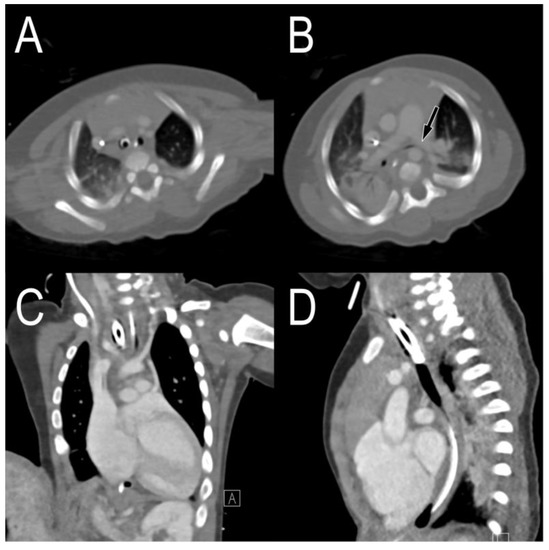

2.1. Case 1

2.2. Case 2